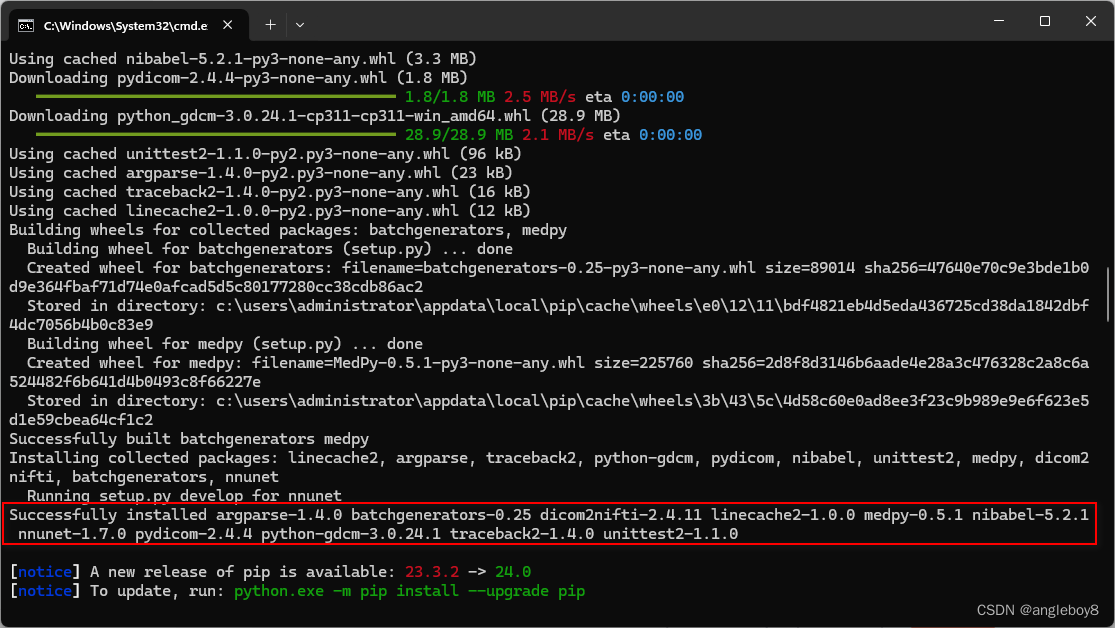

1.本博客是在win11安装,前期Anaconda的虚拟环境自己配置好,然后下载好nnUnet v1的安装包,然后解压在该目中运行:

pip install -e .